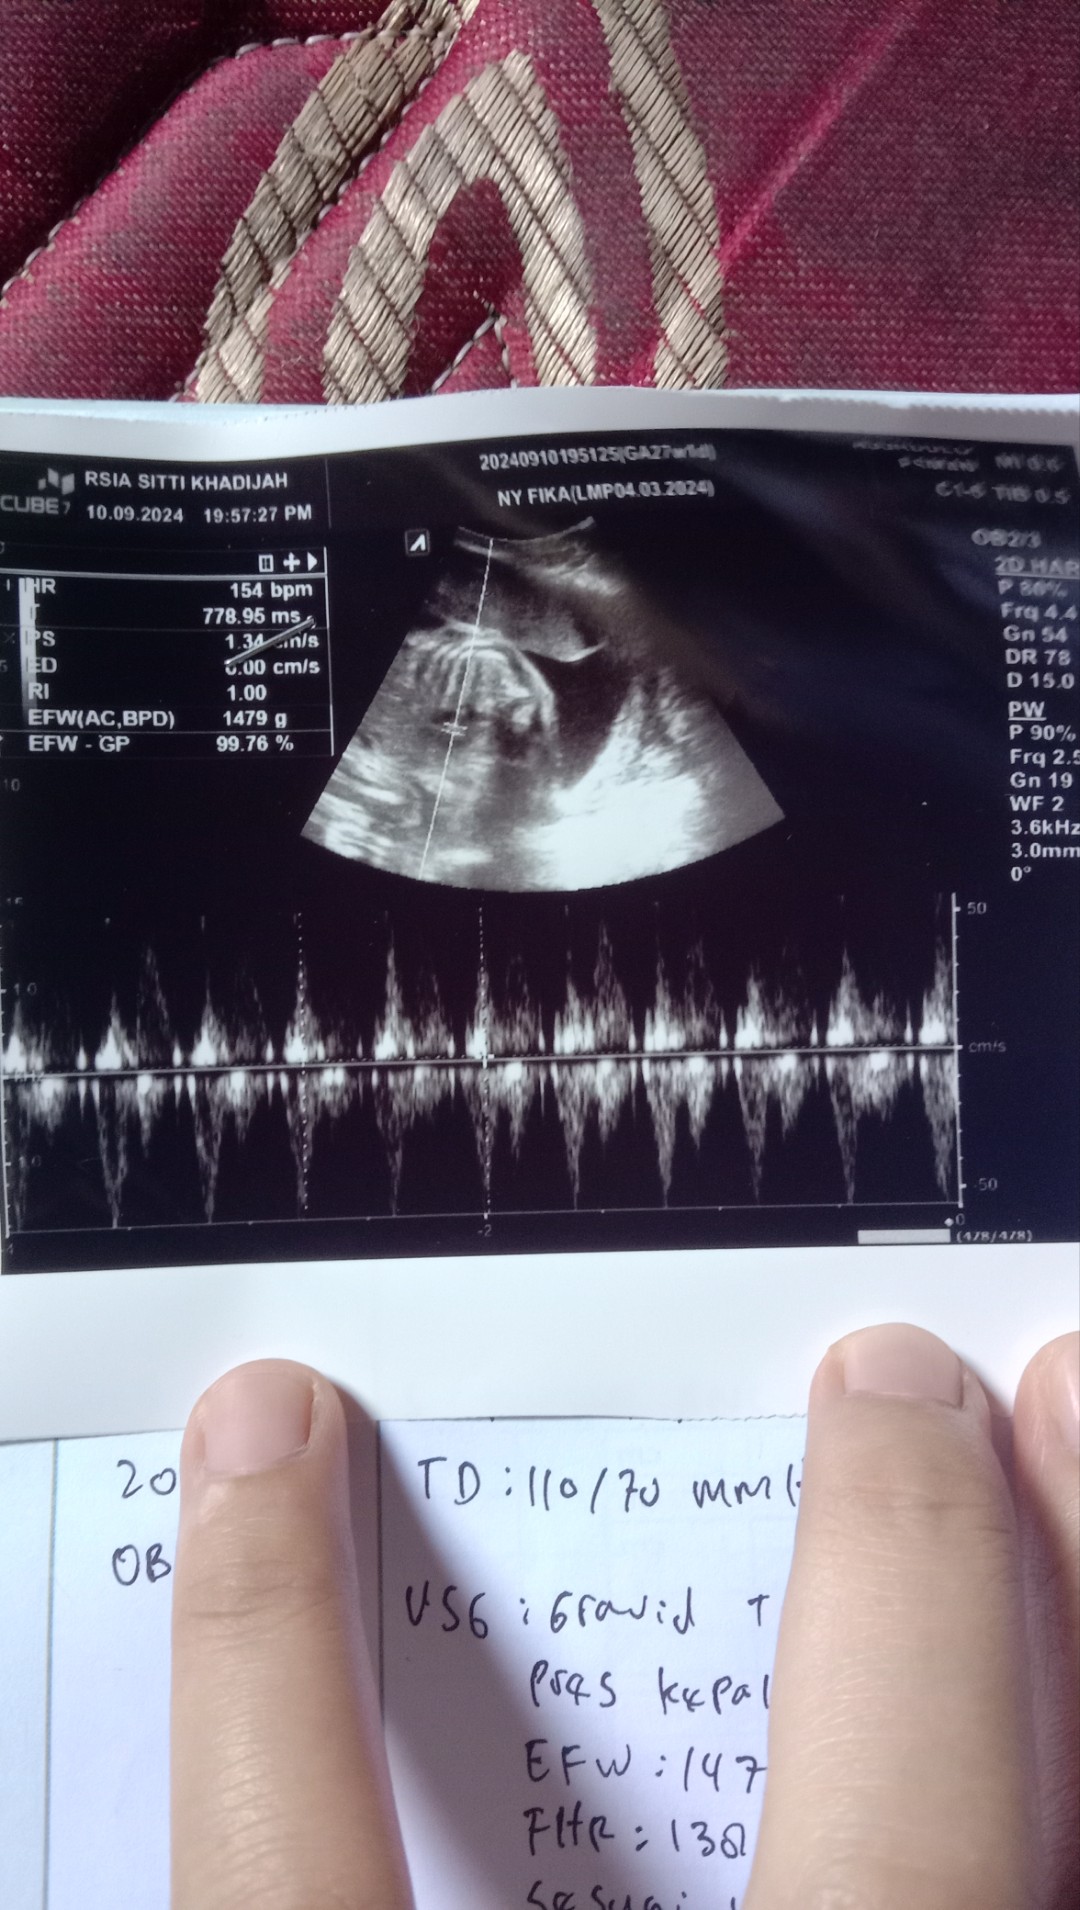

Usg berat bdan janin 27 minggu 1.5grm katanya kurang harus di naikin lagi krn sdh masuk trimestr ke3

aku 27minggu kmrn USG bbj 1,4 grm kata dokter pas gak kegedean gak kurang

4 hari yg lalu hasil usgx in bund